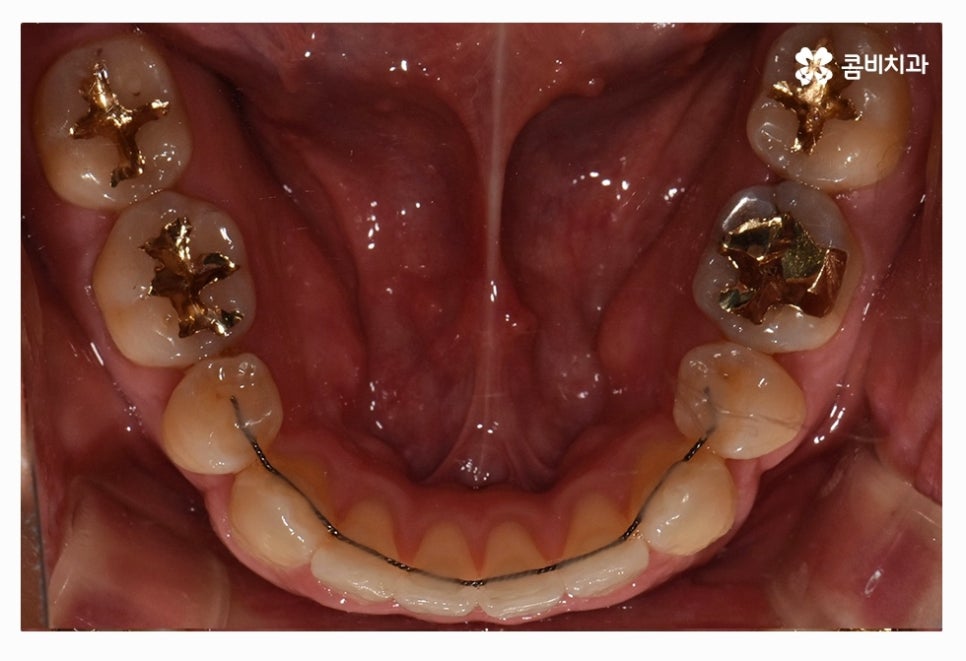

부정교합 환자분들의 경우 발치나 수술이 필요한 경우가 있는데

치아교정을 진행할 때 치아의 이동 공간을 고려해야 하므로

치간 삭제나 어금니 후방 이동으로도 치아 이동 공간이 부족하다면

발치를 필수적으로 해야 하는 경우가 있어요.

간혹 부정교합이지만 앞니 만이라도 가지런해지길 원하시는 분들도

계신데 교합과 얼굴과의 조화를 필수적으로 함께 생각해야 하며

치아교정은 좋은 결과를 얻고 평생 잘 유지해야 하기 때문에

부정교합이신 분들의 경우 전체교정을 해야 하는 경우가 일반적이라고 할 수 있어요.

위 환자는 총 치료기간 약 30개월이 소요되었으며

개인에 따라 치료 기간 및 결과가 차이가 있을 수 있고,

개인에 따라 출혈 및 부작용이 발생할 수 있습니다.